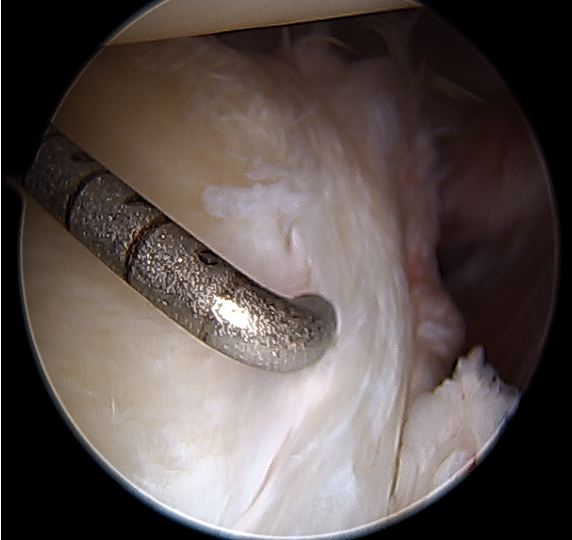

Arthroscopy

Capsule tear anteriorly, extending up into humeral insertion

Side to side suture repair +/- HAGL repair

Beware axillary nerve inferior recess

Side to side repair of capsular tear

Intact anterior labrum with capsular tear, axillary nerve seen below capsular tear in axillary recess